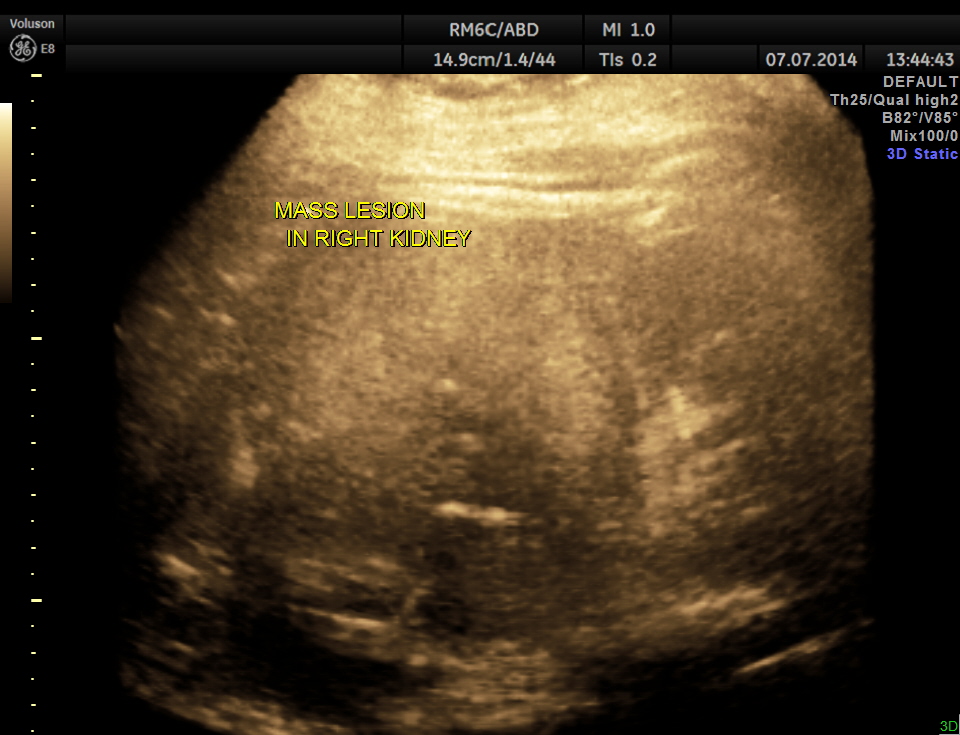

GLASS BODY RECONSTRUCTION shows increased vascularity.

In this patient the increased vascularity is brought out very well by glass body imaging . Clots of blood seen in the urinary bladder gave the false impression of a mass lesion in the bladder initially.The importance of a dynamic study of turning the patient to the sides should always be remembered.